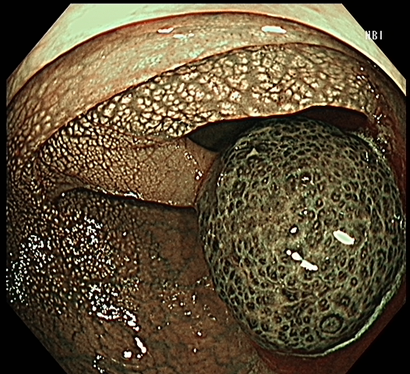

A 30-year-old woman presented with 6-month history of blood-stained stools. The patient denied a family history of colon cancer. Examination was remarkable for blood-streaked stool. A colonoscopy identified a reddish and pedunculated polyp with long stalks in the descending colon measuring 10 × 20 mm macroscopically (Figure 1A), which was well-defined by narrow-band imaging (NBI) magnifying endoscopy (Figure 1B). The solitary bleeding polyp was removed by hot snare polypectomy. Microscopic examination of the specimen demonstrated colonic mucosa with dilated and branched mucin-filled crypts surrounded by stroma containing mixed inflammatory cells (Figure 1C), which was consistent with juvenile polyp. Upper gastrointestinal endoscopy and double-balloon enteroscopy found no polyps in the stomach, duodenum, jejunum and ileum. He had no family history of juvenile polyposis syndrome. A solitary colonic juvenile polyp complicated with bleeding is rare [1]. Because of the potential risk of bleeding, obstruction, and intussusception complicated by giant juvenile polyp, endoscopic resection is recommended.

Figure 1. A. A colonoscopy identified a reddish and pedunculated polyp with long stalks in the descending colon, measuring 10 × 20 mm macroscopically. B. Narrow-band imaging magnifying endoscopy review. C. Microscopic examination of the specimen demonstrated colonic mucosa with dilated and branched mucin-filled crypts surrounded by stroma containing mixed inflammatory cells.